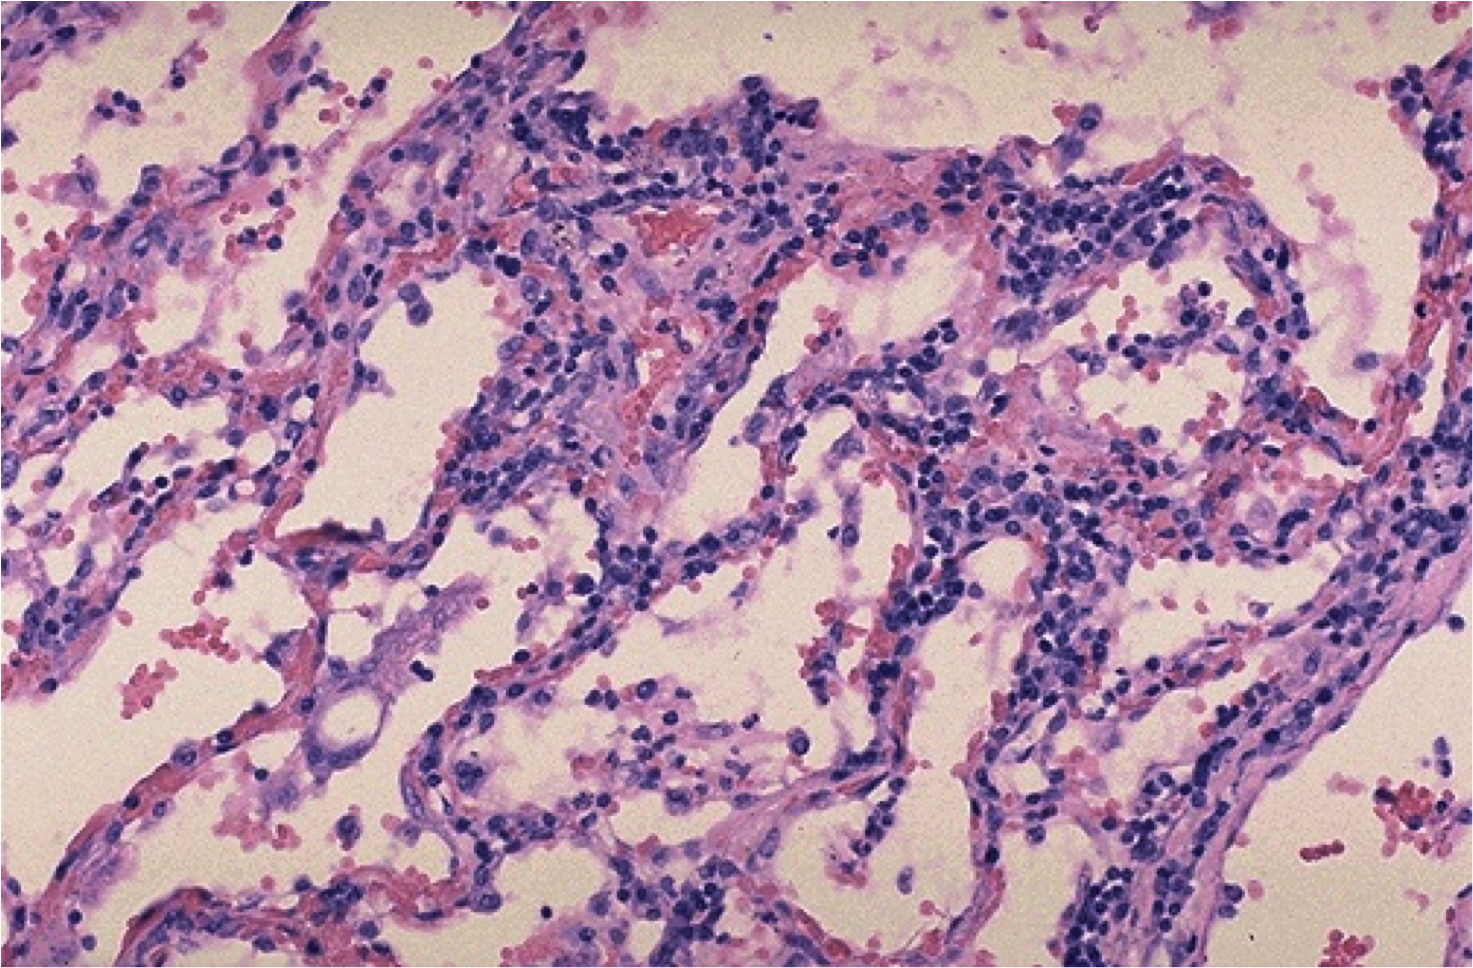

Микроскопический взгляд на мишитарный туберкулез легкого: фотодокументация

Раздел: Снимки-откровения